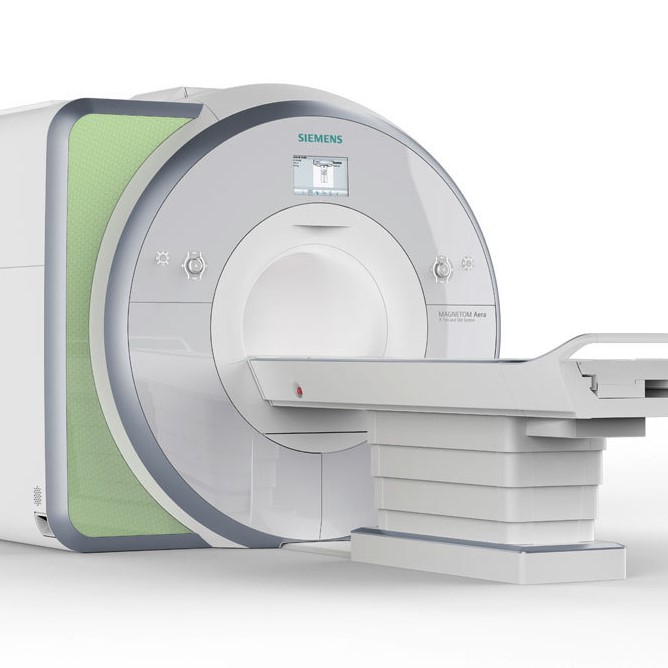

Falls eine Untersuchung von Gehirn oder Wirbelsäule mit Darstellung von Rückenmark und Nervenwurzeln durch Bildgebung erforderlich ist, kann in unser radiologischen Abteilung Kernspintomographie (MRT) oder Computertomographie (CT) erfolgen und das Ergebnis anschliessend mit Ihnen besprochen werden.

Unsere Abteilung für diagnostische Radiologie untersucht mit MRT- und CT- Schnittbilddiagnostik den gesamten Körper für zuweisende Allgemein- und Fachärzte. Für neurologische Fragestellungen werden Gehirn und Rückenmark dargestellt.

oder auch Magnet-Resonanz-Tomografie (MRT) erstellt mit starken Magnetfeldern und Radiowellen hochauflösende Schnittbilder des Körper in beliebiger Ebene. Diese Methode arbeitet ohne Röntgenstrahlen und ohne radioaktive Substanzen.

Wir bieten ein modernes halboffenes MRT-Gerät an, dessen breite Röhrenöffnung auch für Patienten mit Platzangst geeignet ist.